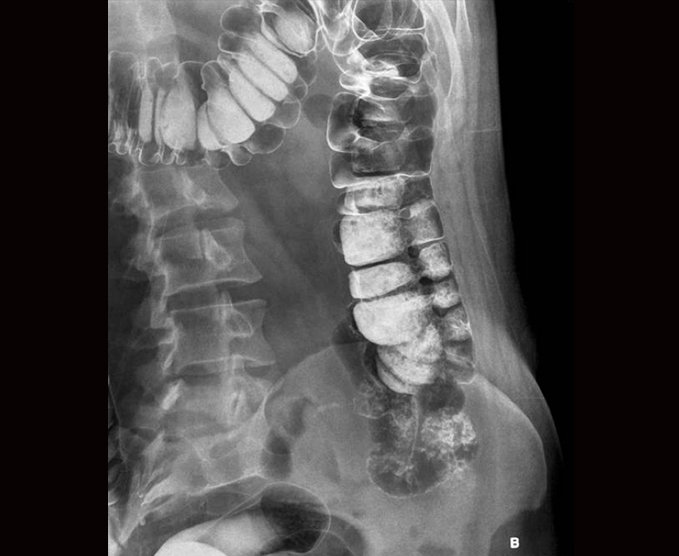

Algunos de nuestros estudios contrastados.

- Urografía excretora